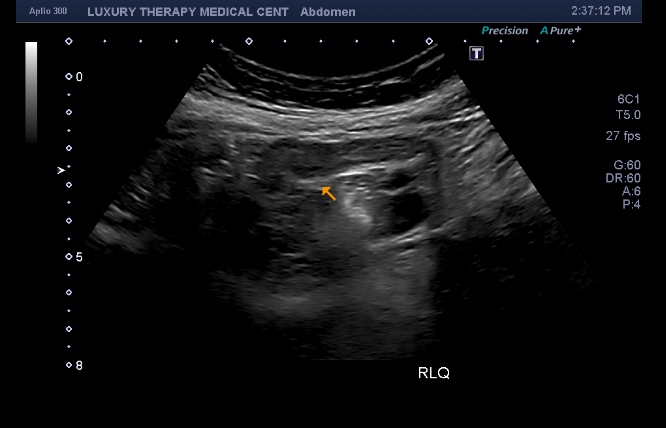

⭐ 2. Tecnología avanzada con imágenes de alta resolución

Contamos con equipos de ultrasonido modernos que ofrecen claridad superior en estructuras abdominales, facilitando diagnósticos más rápidos y exactos.